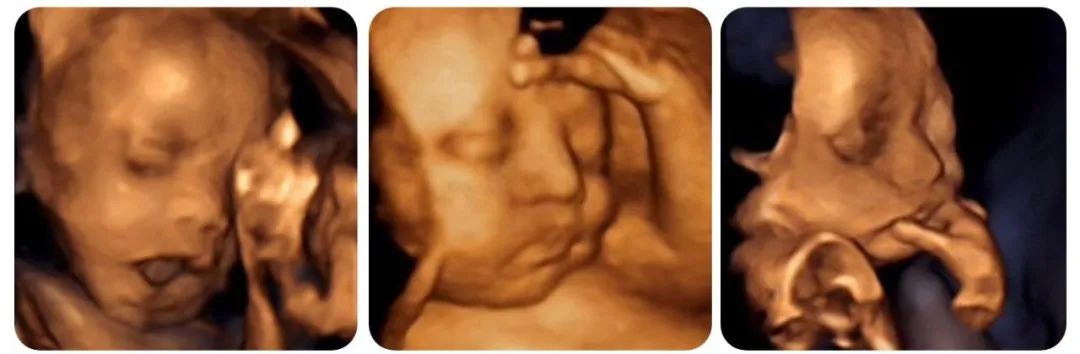

胎儿四维彩超主要是 观察宫内胎儿的生长发育情况,筛查胎儿畸形,为早期诊断胎儿先天性体表畸形和先天性心脏疾病提供准确的科学依据,主要包括以下方面:

1.胎儿面部畸形: 如唇裂、腭裂等。

2.神经系统畸形: 如无脑儿、脑积水、小头畸形、脊柱裂、脑脊膜膨出等。

胎儿四维彩超表面成像还可以直观地看到胎儿在母体内的活动状况,如:呼吸情况,运动情况等。